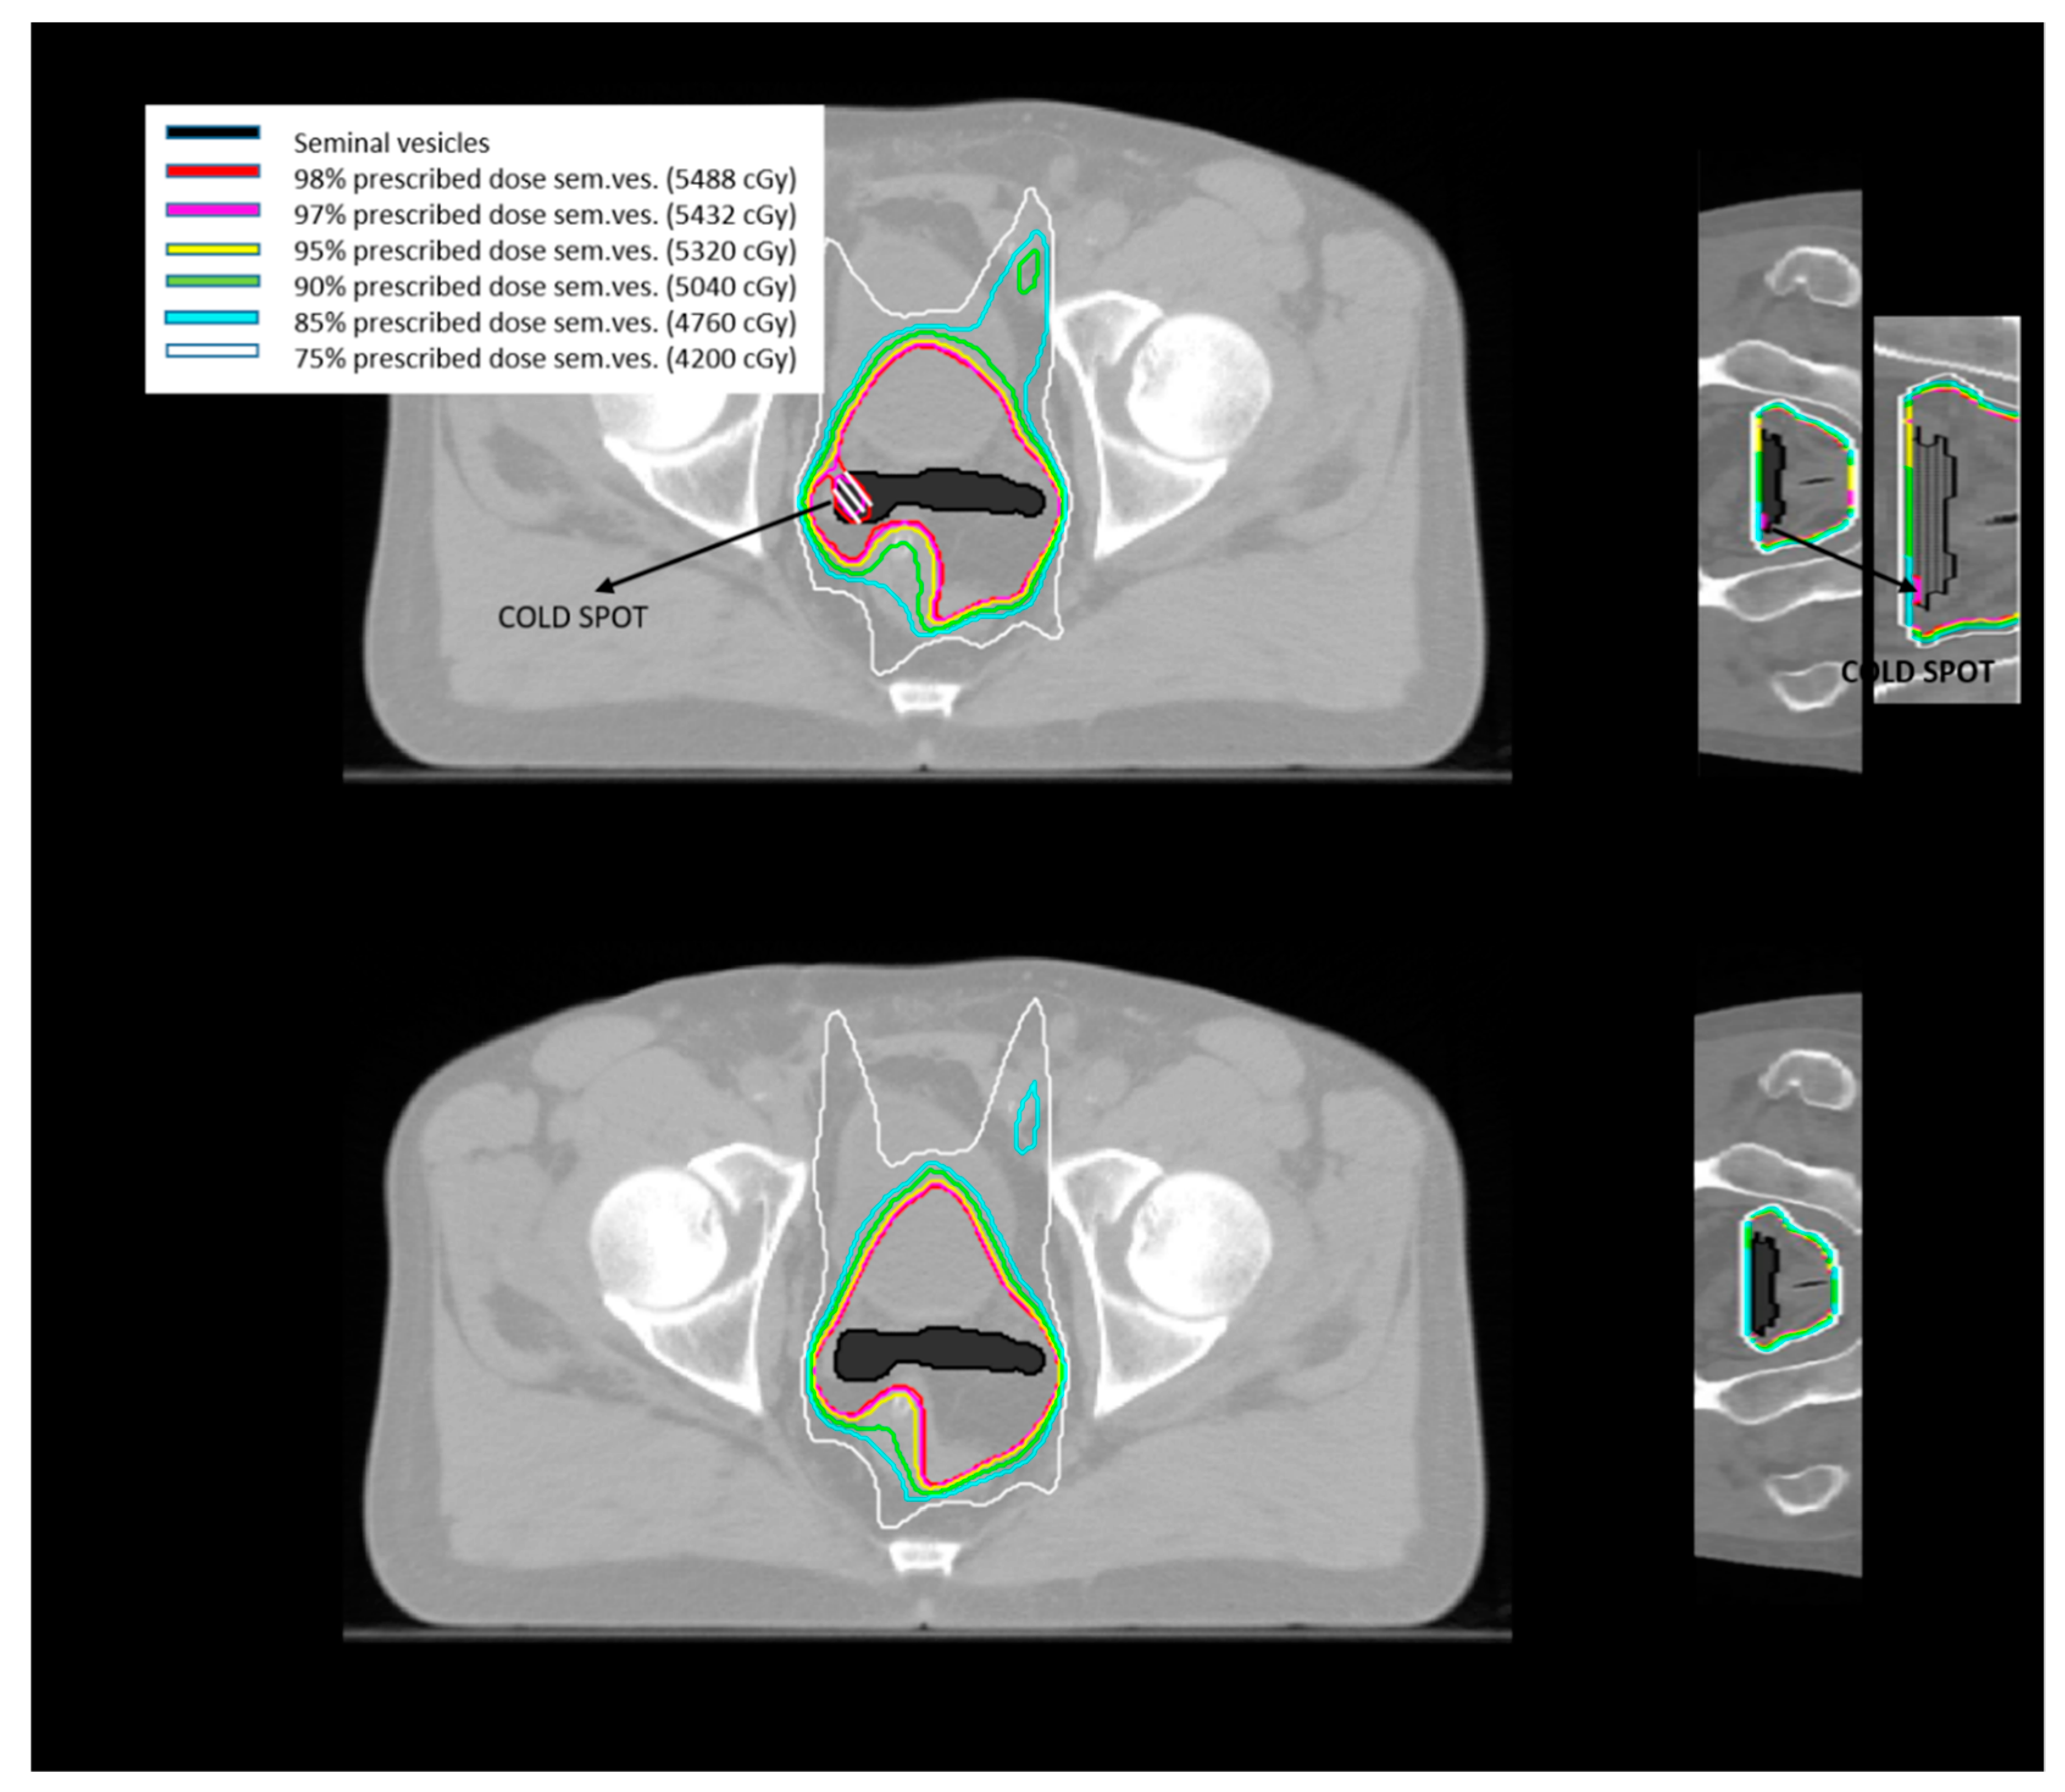

2.1.1. Standard Planning Method on Simulation CT

- Tomé, W.A.; Fowler, J.F. On cold spots in tumor subvolumes. Med. Phys. 2002, 29, 1590–1598. [Google Scholar] [CrossRef]